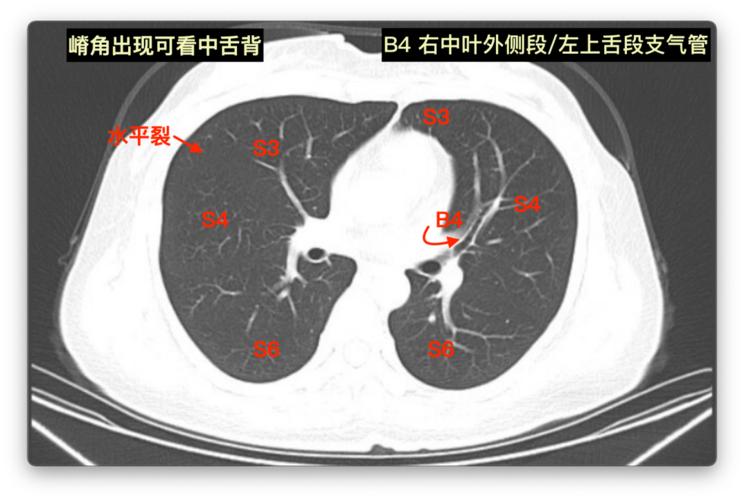

难者不会会者不难之「庖丁解肺」丨一页手册·协和八

看见左右主支气管(双眼)层面:右肺上叶前段和右肺下叶背段,左肺上叶和

右上叶支气管的前面的分支,就是右肺上叶前段支气管;后面的分支,就是